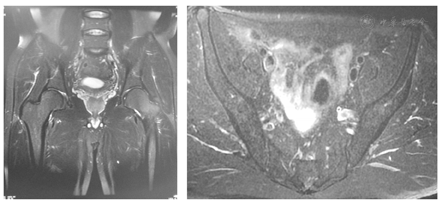

病例2,男,53岁,左髋疼痛半年至疼痛科就诊,活动痛,无法正常行走,VAS为8。左髋关节处叩击痛(+),跛行。曾在其他医院、其他学科就诊,被诊断为"腰椎间盘突出"和"髋关节炎"进行治疗,未见好转,且疼痛逐渐加重,转诊至我科。腰椎磁共振显示为腰椎轻度膨隆,髋关节和骨盆磁共振未见异常,见图3。追问既往史患者有慢性乙肝病史15年,前10年服用拉米夫定(lamivudine)10年,每次10 mg,1次/d;近5年拉米夫定10 mg联合阿德福韦酯10 mg,1次/d。吸取病例1的经验教训,进行血液学生化检测显示血磷0.72 mmol/L(正常值为0.80~1.60 mmol/L),尿酸110 μmol/L(男性正常值为210~430 μmol/L),尿素4.8 mmol/L(正常值为2.5~6.4 mmol/L),24 h尿钙9.73 mmol/24h(正常值为1.3~6.3 mmol/24h),尿蛋白+,尿隐血+++。血沉、碱性磷酸酶均正常,其余检查未见特殊异常。骨密度显示左股骨颈T-score-3.0,Z-score-2.3。排除其他诊断,考虑该患者也是阿德福韦酯致低血磷性骨软化症并伴下腰痛。嘱患者停用阿德福韦酯,继续服用拉米夫定,并口服骨化三醇和碳酸钙D3。1个月后,VAS评分降至1,活动良好。复查血磷0.81 mmol/L,尿酸185 μmol/L,其余化验结果均在正常范围内,见表2。继续治疗随访。